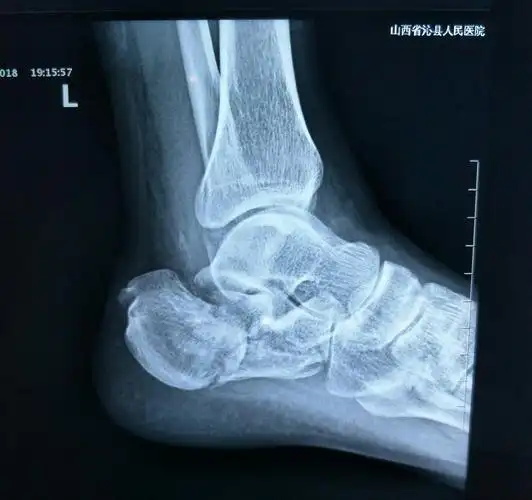

微创撬拨复位空心钉固定治疗跟骨骨折

【足踝篇】 000 右侧跟骨骨折并跟距关节脱位(病例展示)

双侧跟骨骨折

图示:跟骨粉碎性骨折!